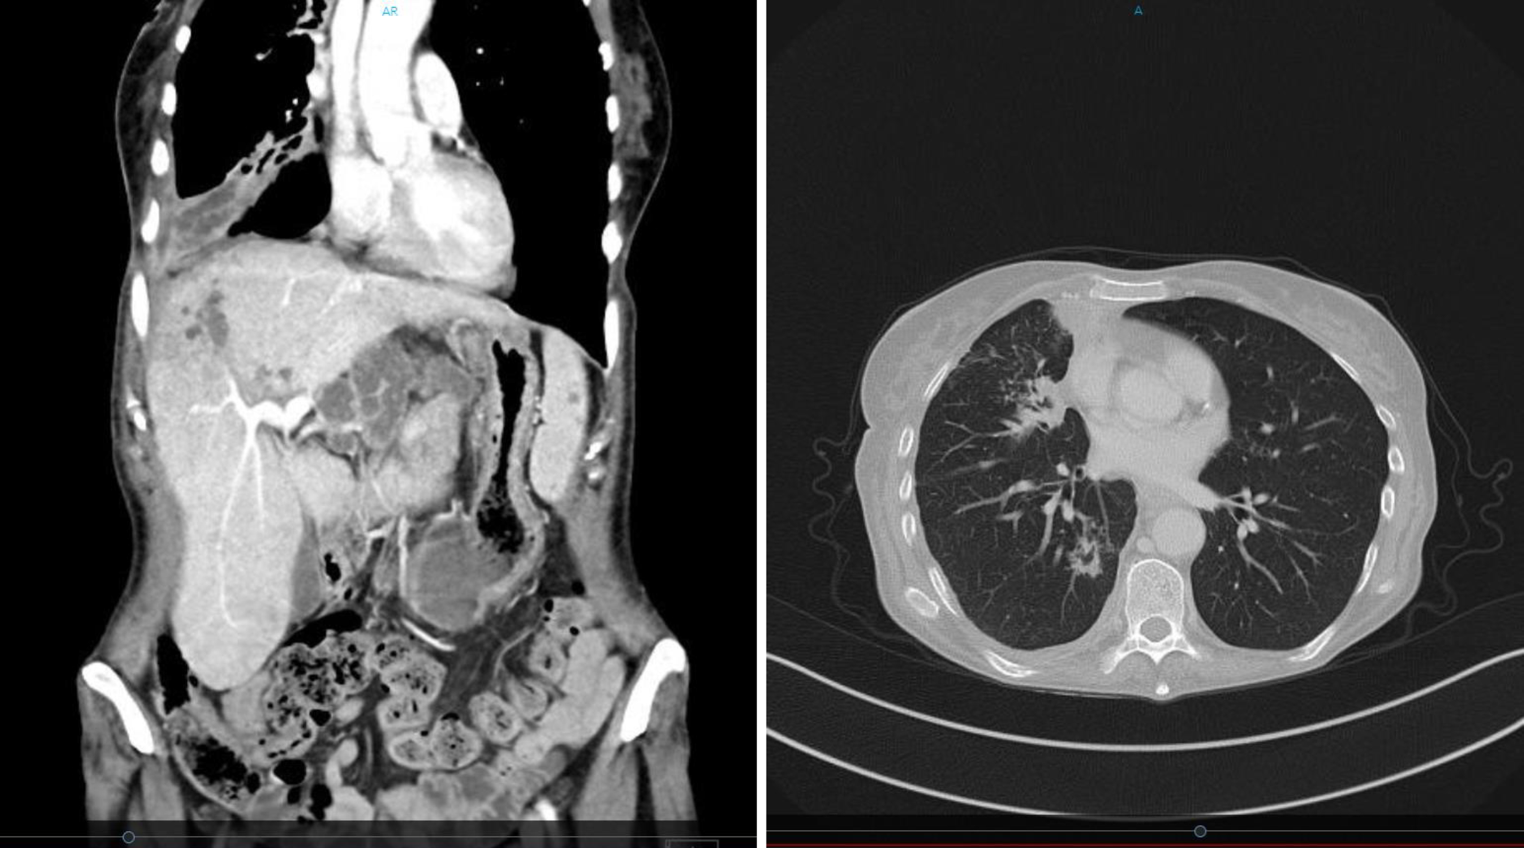

We present the case of a 59-year-old female patient, who presented to the emergency room with fatigue, dyspnea, and fever. Laboratory blood chemistry tests revealed: hemoglobin, 8.5 g/dL; leukocytes, 2.9 G/L; platelets, 84 G/L; C‑reactive protein (CRP), 23 mg/dL; interleukin, 6272 pg/mL; procalcitonin, 2.5 ng/mL; lactate dehydrogenase (LDH), 350 U/L; and an absolute neutrophil count of 0.3 G/L. A computed tomography (CT) scan showed multiple subpleural ventrally arranged, cavernous, cystic, partly disintegrating infiltrates in the upper and middle right lung lobe; morphologically similar lesions on the liver, as well as peripancreatic lesions and in the mesentery. The differential diagnosis corresponded to tuberculosis (Fig. 1).

Fig. 1

Thoracic/abdominal computed tomography scan showing multiple pulmonary and hepatic cavernous, cystic, partly disintegrating lesions